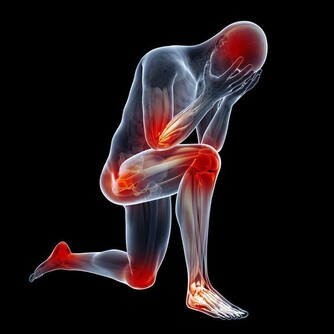

持續肩膀酸疼,需警惕!

肩膀酸疼,是坐辦公室的白領們經常會出現的問題。其實大部分情況也的確是因為長期伏案工作太過於疲勞了。但是如果肩膀酸疼的症狀長期持續而不減緩解。同時還出現了一些其他的並發問題,一定就要提高警惕了。這很可能是肝癌的前兆。

當肝臟腫瘤逐步增大,有可能會壓迫附近的橫膈膜,亦可壓著肺部以下的肌肉神經。而這些被壓著的神經正好是連接右肩的神經,就會引發右肩疼痛。所以,當出現反反复复的右肩膀疼痛時,經過適當的治療,症狀未能好轉,要及時檢查肝臟以排除存在的病變。

僅僅是肩膀疼,就判斷是肝出問題了也是太過武斷。如果同時伴有以下這些情況,那就真得注意了。